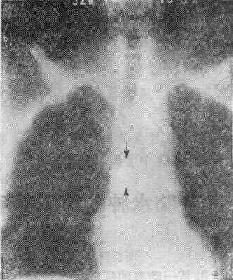

气道肿<a href=瘤(两箭头之间)"/>

113-3 气道肿(两箭头之间)

(四)占位性病变 ①血肿、脓肿是较常见的原因,如咽后壁脓肿;②肿(图113-37),管腔内或管壁良恶性肿如错构、血管等;③气道附近组织器官的肿,如甲状腺的肿压迫侵犯气道。这类原因引致的气道梗阻,一般是慢性进行性的。然而当气道狭窄的程度超过管径的75%以上,由于附加因素如粘痰等可导致急性气道梗阻,产生严重的呼吸困难,甚至窒息死亡。④异物吸入气官。